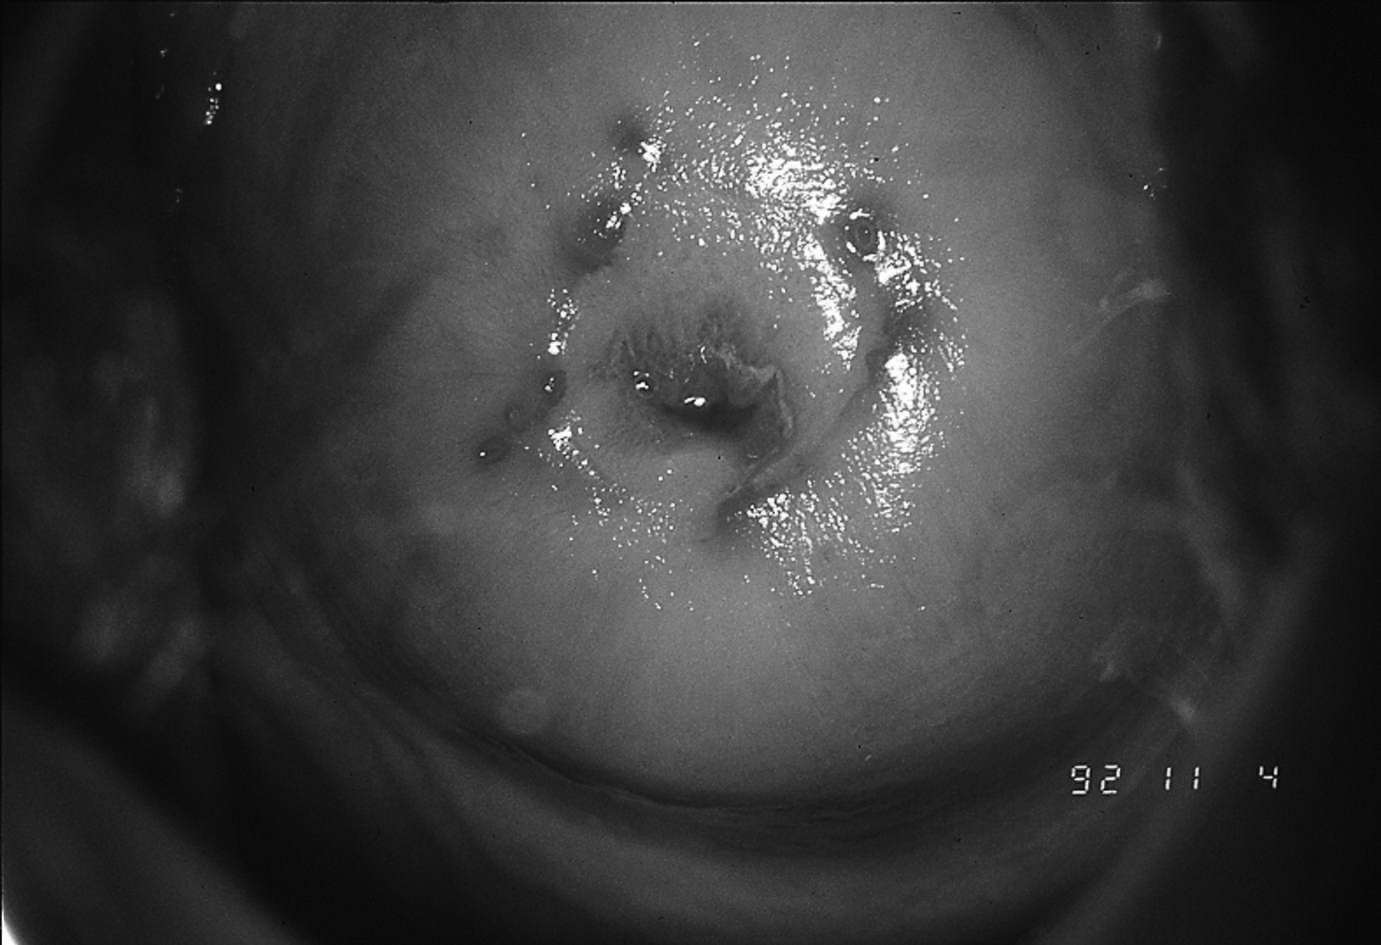

5 . 4  -  Endométriose cervicale

Il s’agit d’îlots de tissus endométrial situés sous un épithelium malpighien normal. L’endométriose se manifeste par des microhémorragies cervicales en période prémenstruelle et se présente sous forme de taches de goudron.

Figure 18.13 Endométriose cervicale

Figure 18.1 Endométriose cervicale.

Elle est souvent secondaire à des traumatismes ou des gestes thérapeutiques cervicaux réalisés trop près des règles.